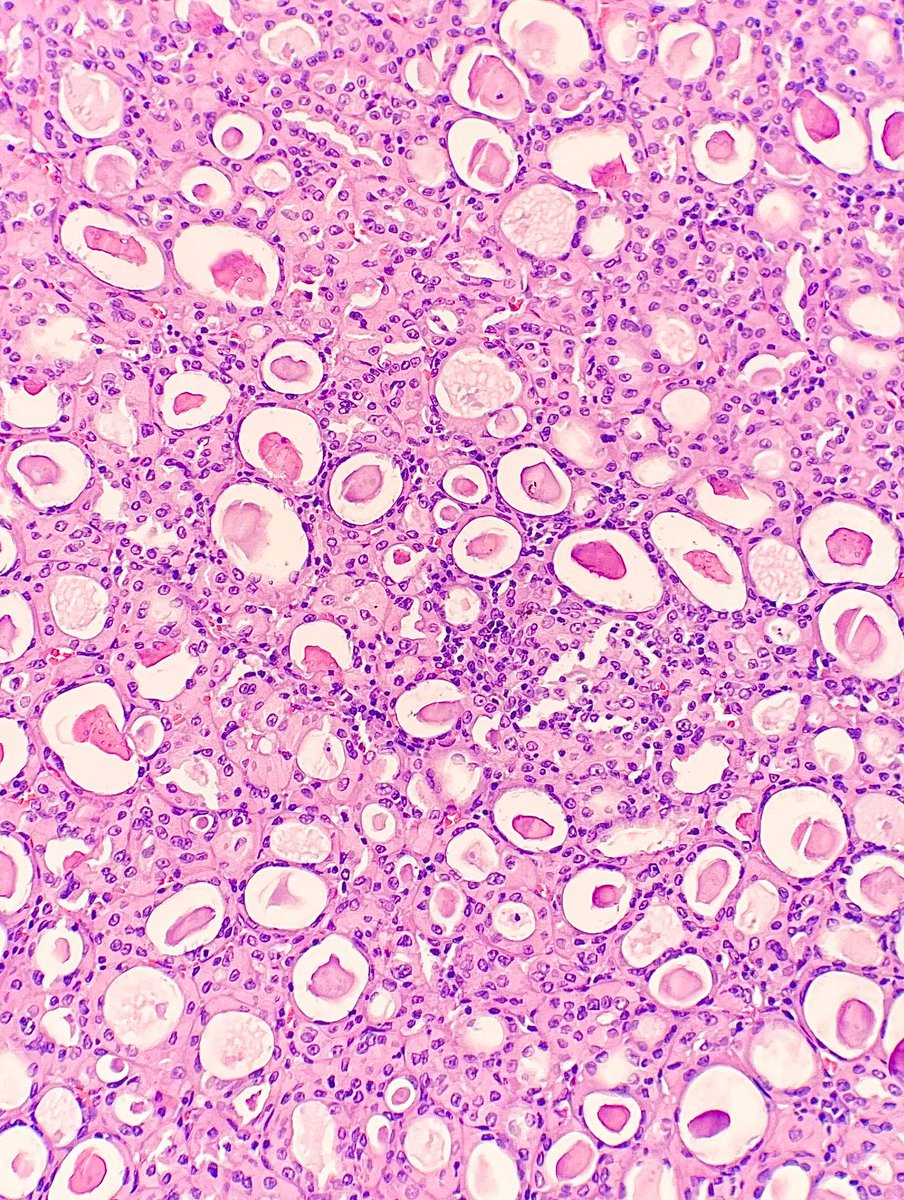

1/4 Dedicated to the memory of Dr Ondrej Hes x.com/GU_Path_Societ… Adult, medullary based kidney tumour - large discohesive polygonal, rhabdoid cells - multinucleated cells - cytoplasmic vacuoles #PathTwitter #PathResidents #Pathology #GUPath Ahmad Dhia GU Pathology Society (GUPS)